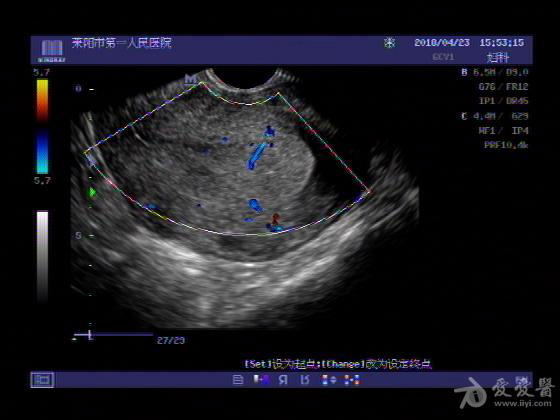

女,48岁,月经量多,两个月,一年前出现过类似现象,刮宫吃药后缓解。

超声可见:子宫内膜显著增厚,后肌壁内膜可见范围约3.27X0.90CM低回声区,CDFI显示较丰富线样血流,宫底宫腔内见类**状低回声结节。前肌壁见多发类圆形低回声结节。

超声提示:子宫内膜增厚(建议刮宫病理),子宫多发肌瘤

病理结果:内膜增生